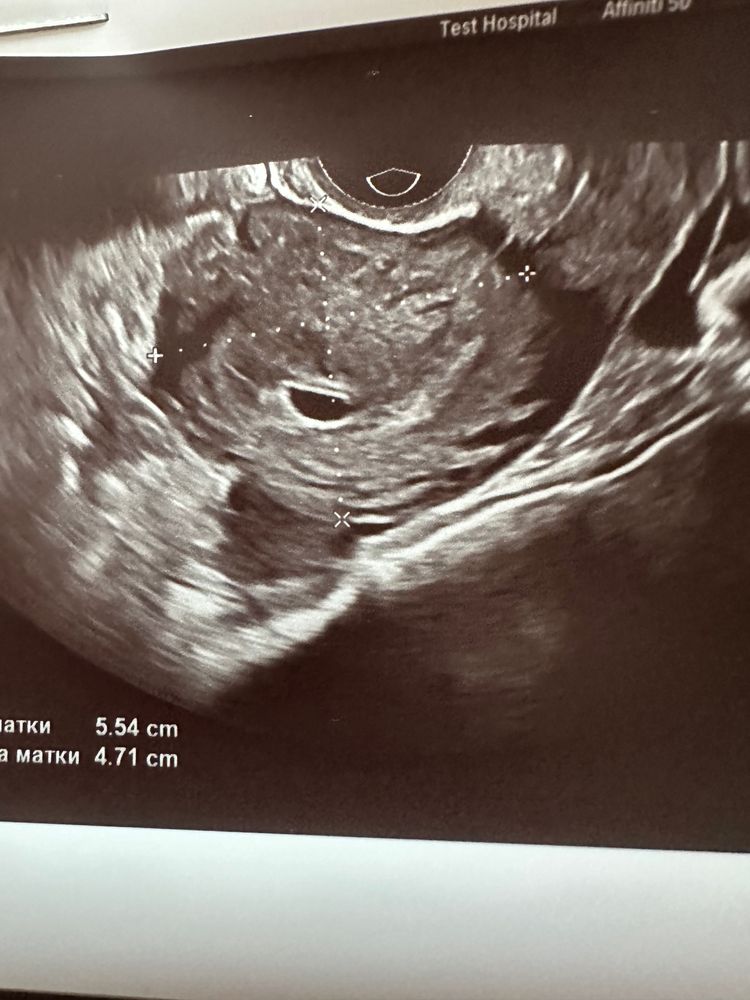

Сабрина, Изображение Изображение А вот узи сегодняшнее

10.08.2023